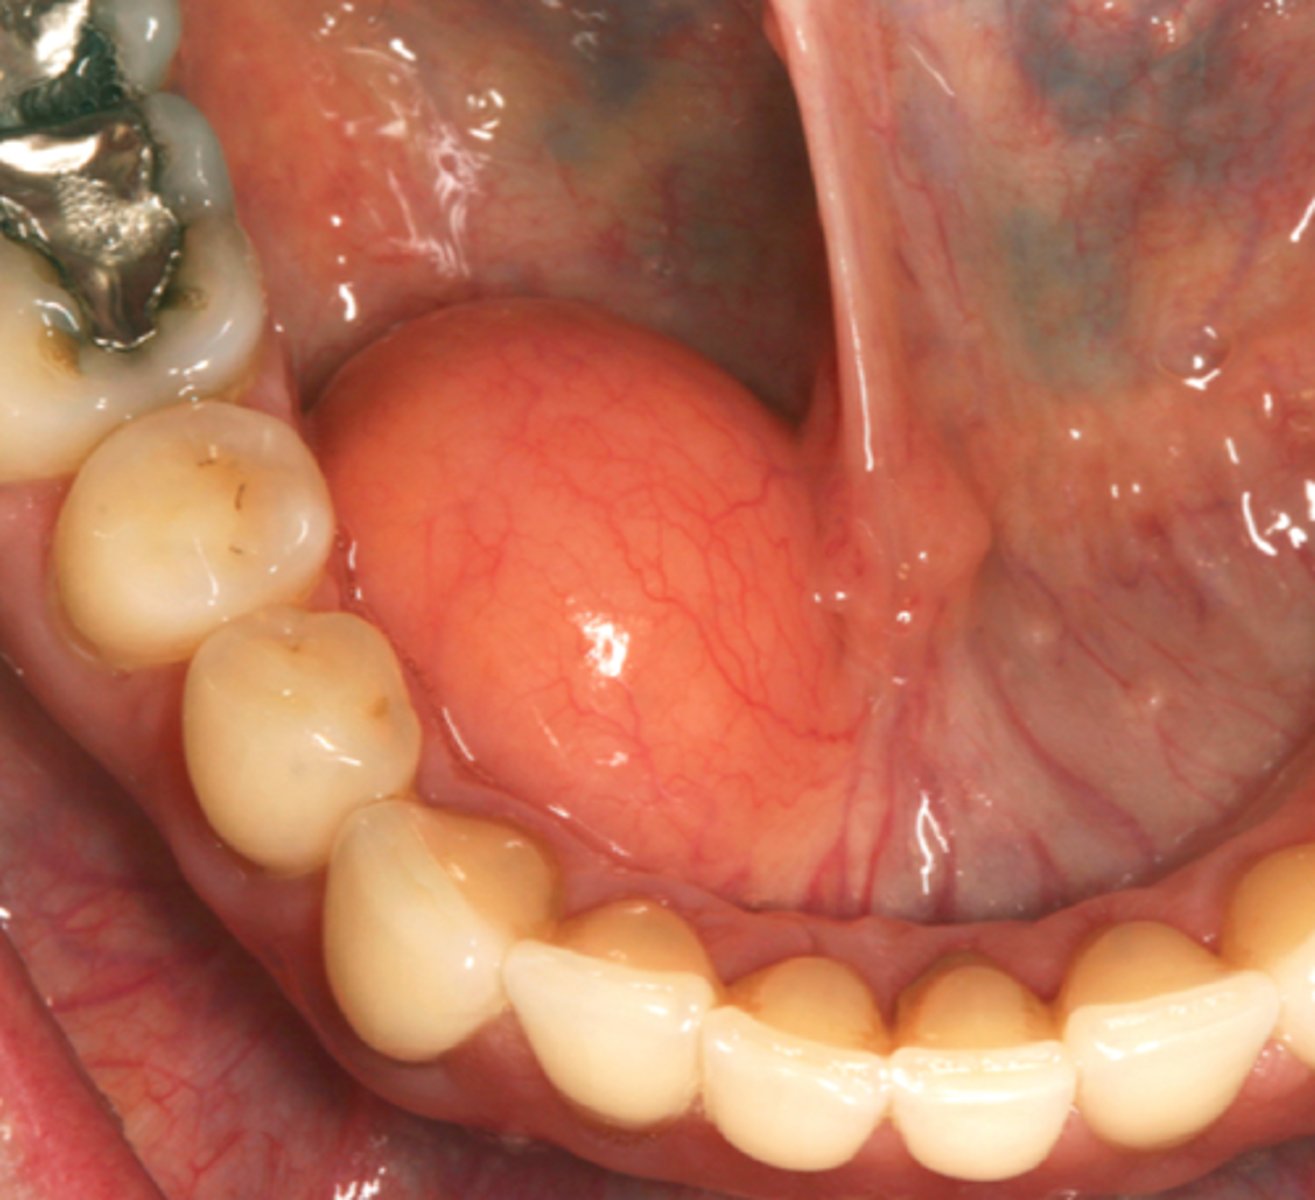

What is a ranula? (+ common location)

large mucocele

⢠common location: floor of mouth - unilateral

⢠blockage of submand/sublingual gland